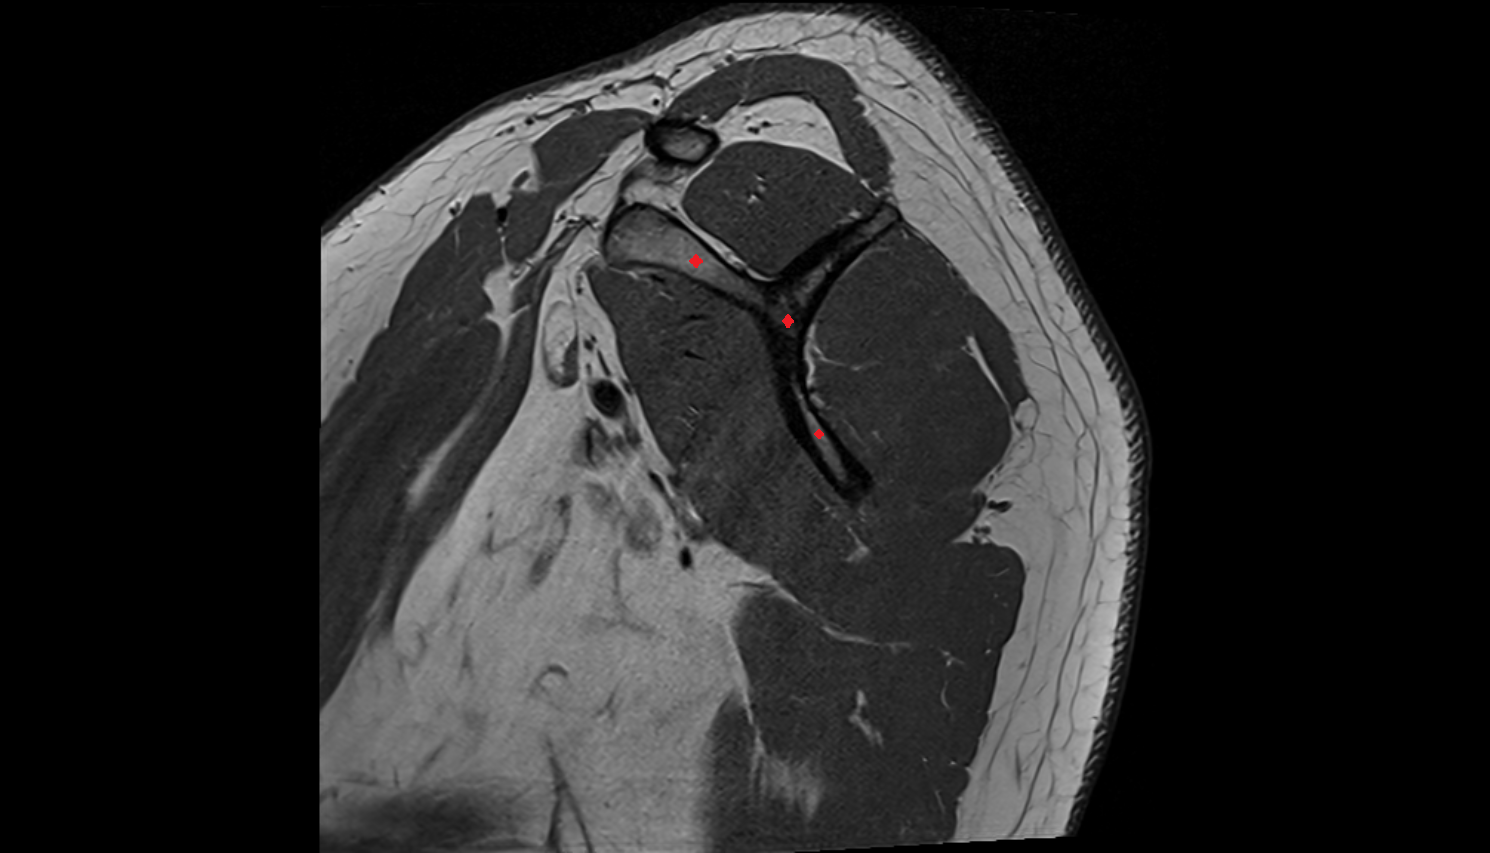

- Glenoid labrum

- Shoulder joint (glenohumeral joint)